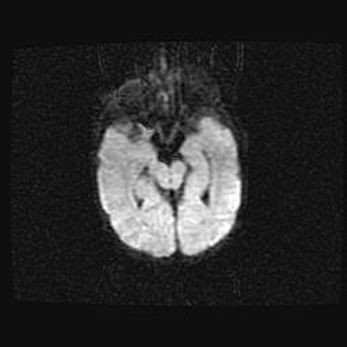

Сообщающаяся гидроцефалия. Кистозная энцефаломаляция головного мозга.

Возраст: 3 месяца 4 дня

Вес: 3100 г

Пол: женский

Окружность головы: 34 см

Срок гестации: 31 неделя

Кистозная энцефаломаляция головного мозга - одна из форм поражения головного мозга в детском возрасте. Характеризуется возникновением множественных и распространённых кист в коре, белом веществе и подкорковых образованиях головного мозга у плодов, новорождённых и детей раннего возраста. Развитие кистозной энцефаломаляции связано с внутриутробной асфиксией и гипотонией, родовой травмой, тромбозом синусов, пороками развития сосудов, инфекциями, сепсисом и другими причинами. Наиболее значимые инфекционные агенты: вирусы простого герпеса, цитомегалии, краснухи, токсоплазмы, энтеробактерии, золотистый стафилококк и другие.